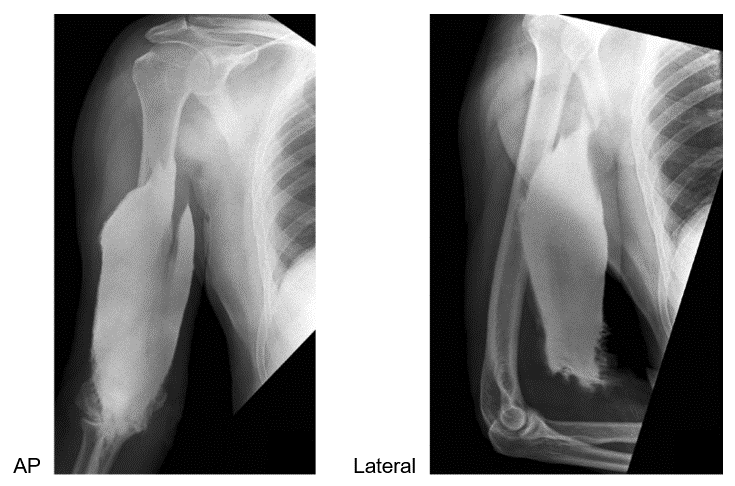

Attenuation is one of the physical principles of radiation interaction. If you recall, it is the reduction in the number of x-ray photons in the beam, and the subsequent loss of energy as the beam passes through the matter (or patient in this instance). In CT, as in diagnostic radiology, the attenuation is dependent on the type of tissue being scanned, such as the soft tissue, the bone, the blood or the muscle. Each type of tissue attenuates a different amount of photons which results in image differences on the finished scan. The denser the tissue, the more the attenuation of the beam.

Let us now look at how the attenuation in a CT scan is measured.

Hounsfield Units of Various Tissues

In 1979 the Nobel Prize was awarded to Godfrey Hounsfield and what was previously known as computed tomography numbers were then named after him. Hounsfield numbers are based on a series of tissue density values calculated by comparing the linear attenuation coefficients of each pixel to that of water. The HU of water is always 0.

This chart demonstrates the average Hounsfield Units of various tissue densities. As we previously stated, the denser the material irradiated, the more the attenuation that occurs in that tissue. By looking at this chart we can see that the denser the tissue, the higher the Hounsfield number assigned, making that area appear more radiopaque or white on the image. The less-dense the tissue irradiated, the smaller the Hounsfield number assigned, causing the area to look more radiolucent or black.